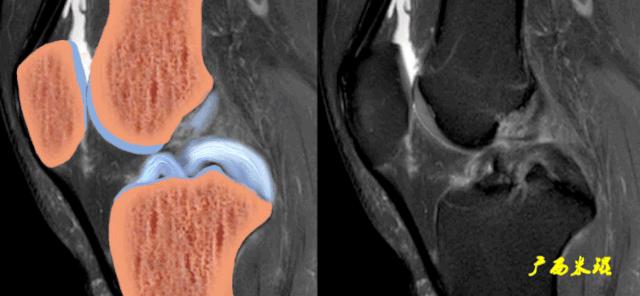

4、横断面表现

横断面PCL表现为扁平椭圆形、半圆形、类圆形或者扇形低信号影,边缘清晰,内部纹理清楚,位于髁间窝区域。